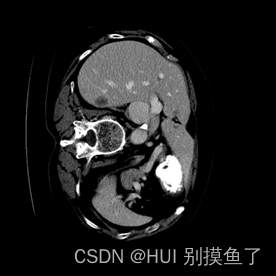

本文数据集为Lits2017肝脏和病灶的分割。标签为(0 1 2)。此数据集为增强CT,所以需要进行窗口的处理。具体参考【医学图像预处理过程】

注: 上面的标签图是自己赋值进行可视化的,实际是[0 1 2 ],根据自己数据集的情况查看mask值:

分析: 分割出肝脏(灰色)、肿瘤(白色),再加上黑色背景,相当于是一个三分类问题。